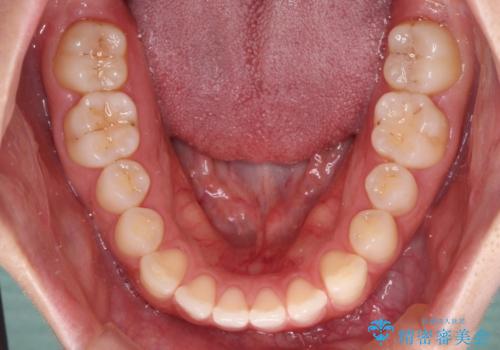

すきっ歯とオープンバイト インビザライン・ライトで改善

- 食いしばりによる顎の負担を気にして来院された患者様です。

当初は、ボツリヌス毒素による咬筋の過緊張の緩和と、睡眠時のマウスピース装着による咬合負担の解消を行いました。

オープンバイトのため、奥歯に負担のかかる咬合状態であったので、矯正治療を提案したところ、希望をされました。

すきっ歯程度の軽度の歯列不正であったため、インビザライン・ライトにより咬合改善を行うこととしました。

オープンバイトやすきっ歯は、舌突出癖によりあっという間に後戻りをするため、矯正治療前からトレーニングを行っていただき、更には後戻り防止のワイヤーリテーナーを併用しています。